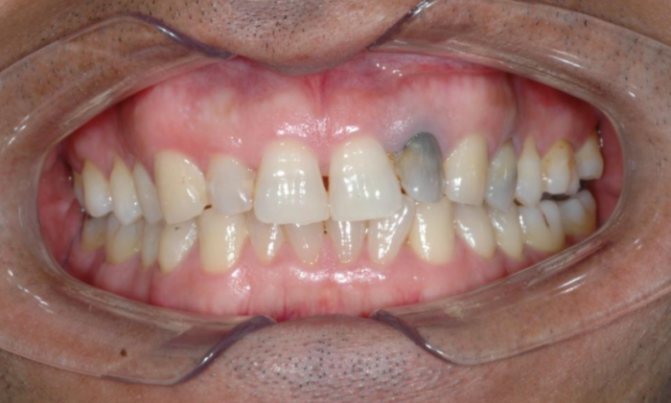

Диагностику заболевания врач стоматолог проводит с помощью основных и дополнительных методов исследования. В первую очередь проводится осмотр больного зуба. Если возле пломбы образуется полость или через эмаль просвечивает кариозный процесс, этих признаков будет достаточно для определения заболевания. Также специалист собирает анамнез болезни, спрашивает о первичном лечении.

Если стоматолог увидит, что пломба изменила цвет, но не сможет сразу определить кариес, он назначит рентгенологический снимок. Рентген также понадобится в случае, если вторичный кариес возник в депульпированном зубе.

С помощью рентгена можно оценить глубину и локализацию кариозного разрушения. На снимке пломба будет выглядеть как белое пятно, а кариес – как темное.

Нередко наблюдается кровоточивость десны у поражённого зуба, ломота в области челюсти. Выявить кариозное поражение костной ткани можно и визуально. Стоит обратить внимание на пломбу. Нередко она меняет цвет или по её краям появляется тёмный коричневый ободок. Также наблюдается образование щелей и сколов зубной эмали.

О развитии вторичного (рецидивирующего) кариеса говорят, когда патологический процесс начинает развиваться под недавно зафиксированной пломбой, вкладкой или коронкой. То есть после любого лечения. В результате зуб постепенно изменяет свой окрас, и самой частой причиной тому становится некачественно проведенное лечение. Происходит рецидив болезни, который в подавляющем большинстве случаев становится следствием оставления зазора между зубными тканями и пломбировочным материалом. Или же некачественно проведенного очищения полости от воспаленных тканей.